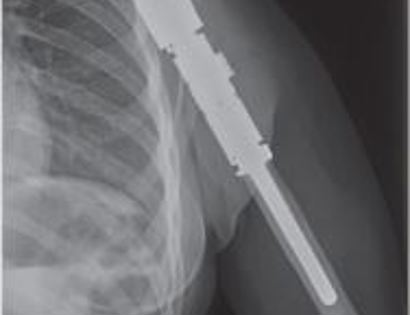

X-Ray of Endoprosthesis